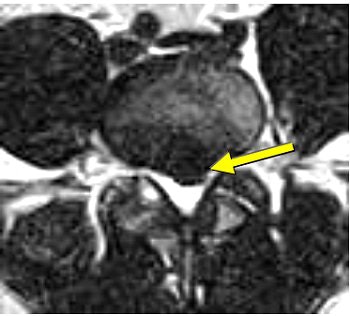

| Same patient as above. Top, transaxial T2-weighted image showed left L4 spinal nerve root compromise with axial loading (below). |